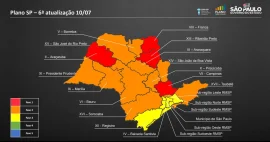

Com melhora de índices, dez regiões progridem de fase no Plano SP; Bauru permanece na vermelha

Região de Bauru é reclassificada para a fase laranja do Plano SP; Marília retrocede para a vermelha

Região de Marília retrocede para a Fase Laranja do Plano São Paulo

Em primeiro decreto como prefeita, Suéllen mantém Bauru na fase amarela do Plano SP

Após três dias em Fase Vermelha, estado de SP volta à Amarela

João Dória reclassifica todo o estado para a fase vermelha do Plano São Paulo